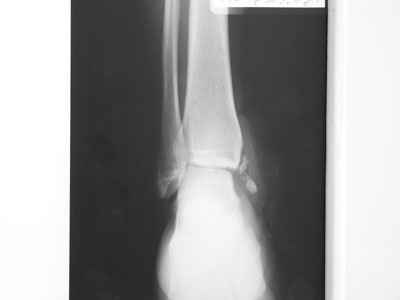

Совершенно верно был такой Пациент парень 29 лет. Только не 2 года а 4 года назад. Лечение растянулось на 2 этапа. На момент сообщения наложил окончатую гипсовую повязку, мазевые повязки, грануляции, закрыл свободной кожной пластикой. Через 2 месяца рана закрылась рубцом, гипс снял отправил на ЛФК. В течение года появлялся дважды - все ОК, нестабильности в суставе не было. Пациент работник УВД - его даже не комисовали. Обратился через 2 года после повторной травмы (опять мотоцикл) - открылся свищ в области медиальной лодыжки. Проведена операция - санация, рубец иссечен, пластика суральным лоскутом - состоятельная. Аппарат Илизарова на 2 месяца. Аппарат демонтировали опять ЛФК - Нестабильности в суставе нет, до сих пор трудится в органах... Опять подумывает о покупке мотоцикла.

К сожалению снимки нашел только после пластики. Р-гр где-то утерял посмотрю не работе.

Нашел в архиве форума снимки от 2007 года. Классная штука интернет! Александру Николаевичу отдельное спасибо!